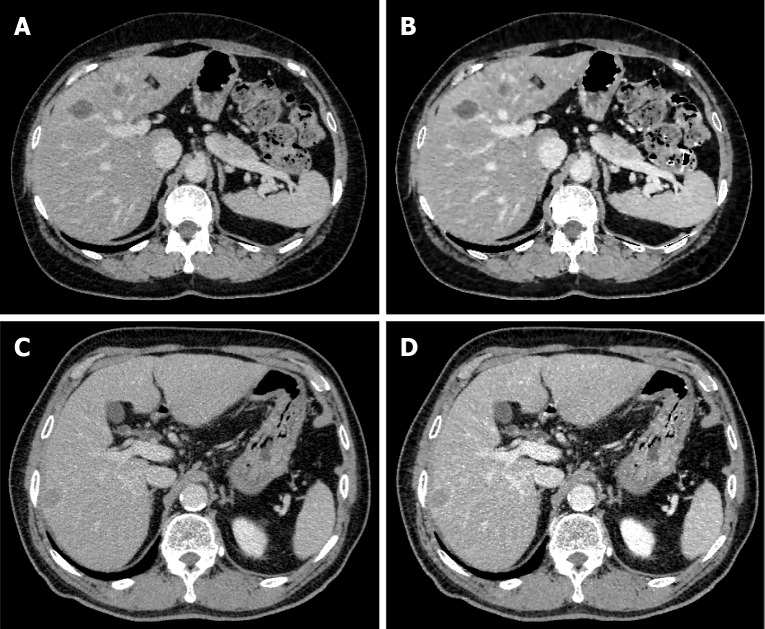

背景:三相动态计算机断层成像在肝脏区域特别有用。然而,造影剂动态成像的缺点是由于多次成像会增加辐射暴露。我们假设对比增强增强(CE-boost)技术可以增强平衡期(EP)图像的对比度,并产生类似于门静脉期(PVP)图像的增强,如果这是可能的,EP成像可以发挥与PVP成像相同的作用。我们还推测,这可能使三相动态成像转换为双相动态成像,减少患者的辐射暴露。目的:确定EP的CE-boost, CE-boost (EP)是否比常规图像有用。方法:回顾性分析2016年1月至2022年10月在我院诊断为肝癌的52例患者。从这些计算机断层图像中,从EP和平面图像生成CE-boost图像。我们根据对比噪声比(CNR)、信噪比和品质系数(FOM)比较了血管和肝实质的PVP、EP和CE-boost (EP)。还进行了血管可视化、病变显著性和图像噪声的视觉评估。结果:除肝实质外,CE-boost (EP)图像在CNR、信噪比和FOM方面均优于PVP图像。肝实质内CNR和FOM比较无显著差异(P = 0.62, 0.67)。EP和CE-boost (EP)图像的比较一致地倾向于CE-boost (EP)。在视觉评价方面,CE-boost (EP)图像在病变显著性方面明显优于PVP图像,在图像噪声方面明显优于PVP图像。CE-boost (EP)图像在门静脉节段性分支的血管显示和病变显著性方面明显优于EP图像,在图像噪声方面优于EP图像。结论:CE-boost (EP)图像质量与常规PVP和EP相当或优于常规PVP和EP。CE-boost (EP)图像可能提供与传统PVP相当的信息。

Methods: We retrospectively analyzed the cases of 52 patients who were diagnosed with liver cancer between January 2016 and October 2022 at our institution. From these computed tomography images, CE-boost images were generated from the EP and plane images. We compared the PVP, EP, and CE-boost (EP) for blood vessels and hepatic parenchyma based on the contrast-to-noise ratio (CNR), signal-to-noise ratio, and figure-of-merit (FOM). Visual assessments were also performed for vessel visualization, lesion conspicuity, and image noise.

Results: The CE-boost (EP) images showed significant superiority compared to the PVP images in the CNR, signal-to-noise ratio, and FOM except regarding the hepatic parenchyma. No significant differences were detected in CNR or FOM comparisons within the hepatic parenchyma (P = 0.62, 0.67). The comparison of the EP and CE-boost (EP) images consistently favored CE-boost (EP). Regarding the visual assessment, the CE-boost (EP) images were significantly superior to the PVP images in lesion conspicuity, and the PVP in image noise. The CE-boost (EP) images were significantly better than the EP images in the vessel visualization of segmental branches of the portal vein and lesion conspicuity, and the EP in image noise.